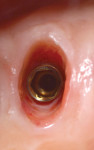

Surgical treatment required atraumatic tooth removal without flap elevation, thereby maintaining the periosteal blood supply to the interproximal and residual labial bone plate. Sharp dissection of the supracrestal fibers was performed with a 15c scalpel blade prior to tooth extraction, and the socket was thoroughly debrided with a surgical spoon excavator (Figure 9). The partial absence of the labial bone plate was evident (Figure 9), yet the soft tissue was completely intact. A tapered platform-switched internal connection-type implant (Biohorizons Plus, Biohorizons, biohorizons.com) was placed 4 mm below the FGM to allow greater vertical distance (ie, running room) for the proper submergence profile of the custom two-piece healing abutment (Figure 10). Primary stability was achieved through engagement of the lateral proximal walls of the first bicuspid socket and confirmed with hand-torque of 50 Ncm to facilitate immediate fabrication of a custom healing abutment.

A healing period of 8 months was specified for this patient to allow the reconstitution of the buccal plate before final impression-making of implants Nos. 12 and 13. A CBCT was also taken to confirm radiographic healing of the newly generated buccal bone plate (Figure 16). After first disconnection of the two-piece custom healing abutment, the anatomy of the reconstituted and maintained gingival architecture of the extraction socket was evident (Figure 17 and Figure 18). Single-unit, screw-retained, ceramic-metal implant restorations were fabricated for implants Nos. 12 and 13, as well as full-coverage crowns for natural teeth Nos. 14 and 15 (Figure 19 and Figure 20). A final periapical radiograph was taken after insertion of the definitive single-unit restorations on the upper left sextant of the patient’s dentition (Figure 21).